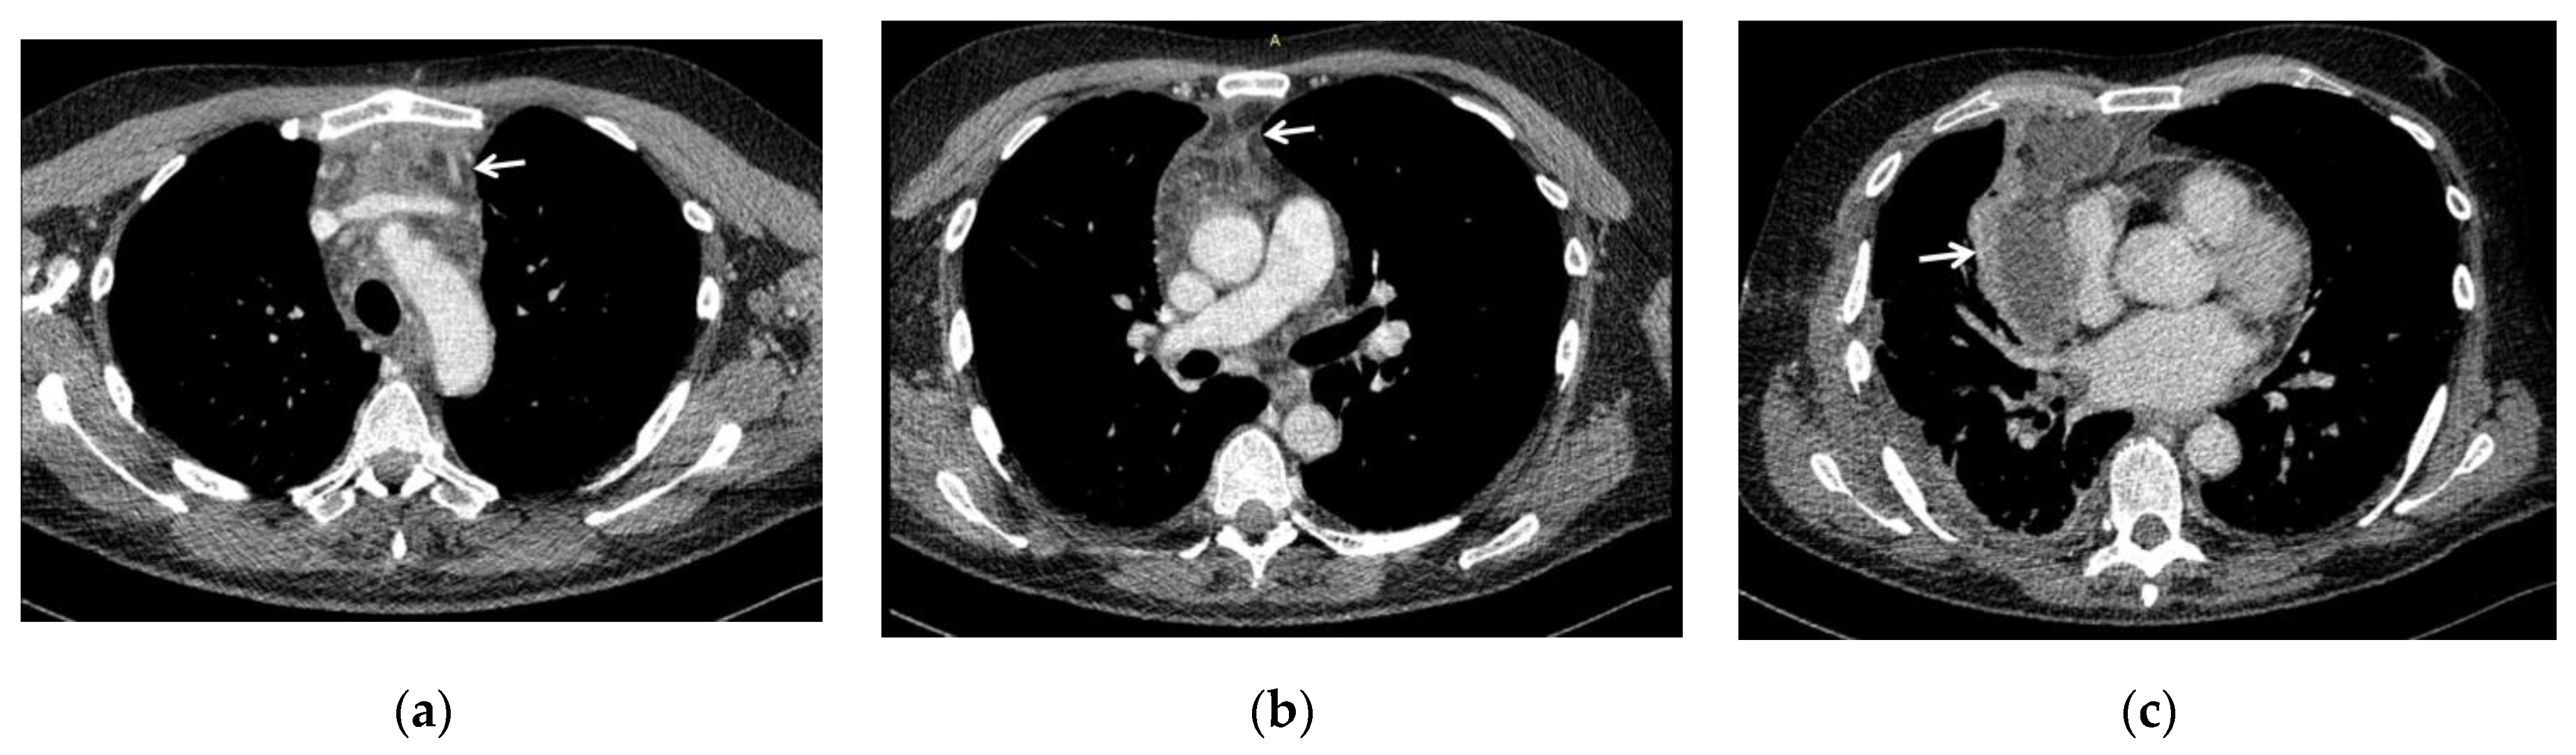

The degree of diffusion of DNM according to Endo’s classification, defined using CT scans and intra-operative findings (Figure 1), was distinguished as follows: type I in 6 patients, type IIA in 6 and type IIB in 3.

The spread of infection was evaluated according to Endo’s classification of DNM [7,8]: type I (DNM localized in the upper mediastinum above the tracheal bifurcation); type IIA (DNM extends to the lower anterior mediastinum); type IIB (DNM extends to the anterior and lower posterior mediastinum). We found a prevalence of type II cases, overall representing 60%, and specifically, type IIA was found in 40% of patients, whereas type IIB in 20%; consequently type I was found in 40% of cases. However, contrary to what has been argued by some authors in other studies, where there was a clear prevalence or presence only of type II [3,4], we must point out that in our experience, type I was found in a high percentage, probably because of an early diagnosis with a timely treatment, that in fact was successful for all patients (0% mortality rate).

Figure 1. CT scans showing the spread of infection of DNM in three of our patients, evaluated according to Endo’s classification of DNM [7,8]: (a) type I (DNM localized in the upper mediastinum above the tracheal bifurcation); (b) type IIA (DNM extends to the lower anterior mediastinum, below the tracheal bifurcation); (c) type IIB (DNM extends to the anterior and lower posterior mediastinum), with associated right pleural effusion. White arrows indicate the mediastinal involvement.